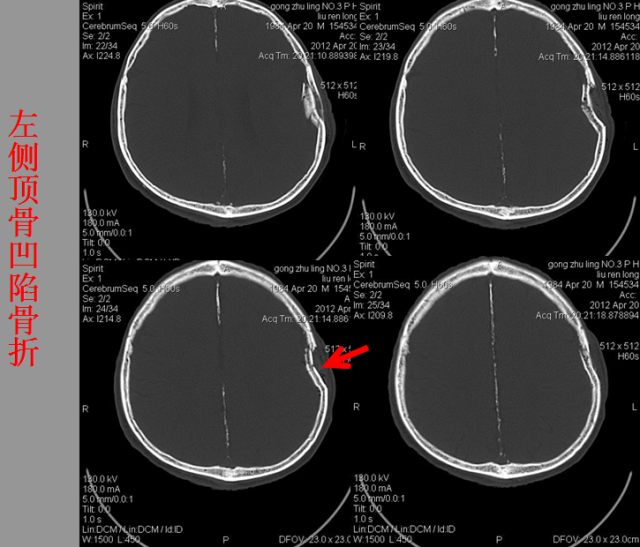

急性颅脑损伤篇

03